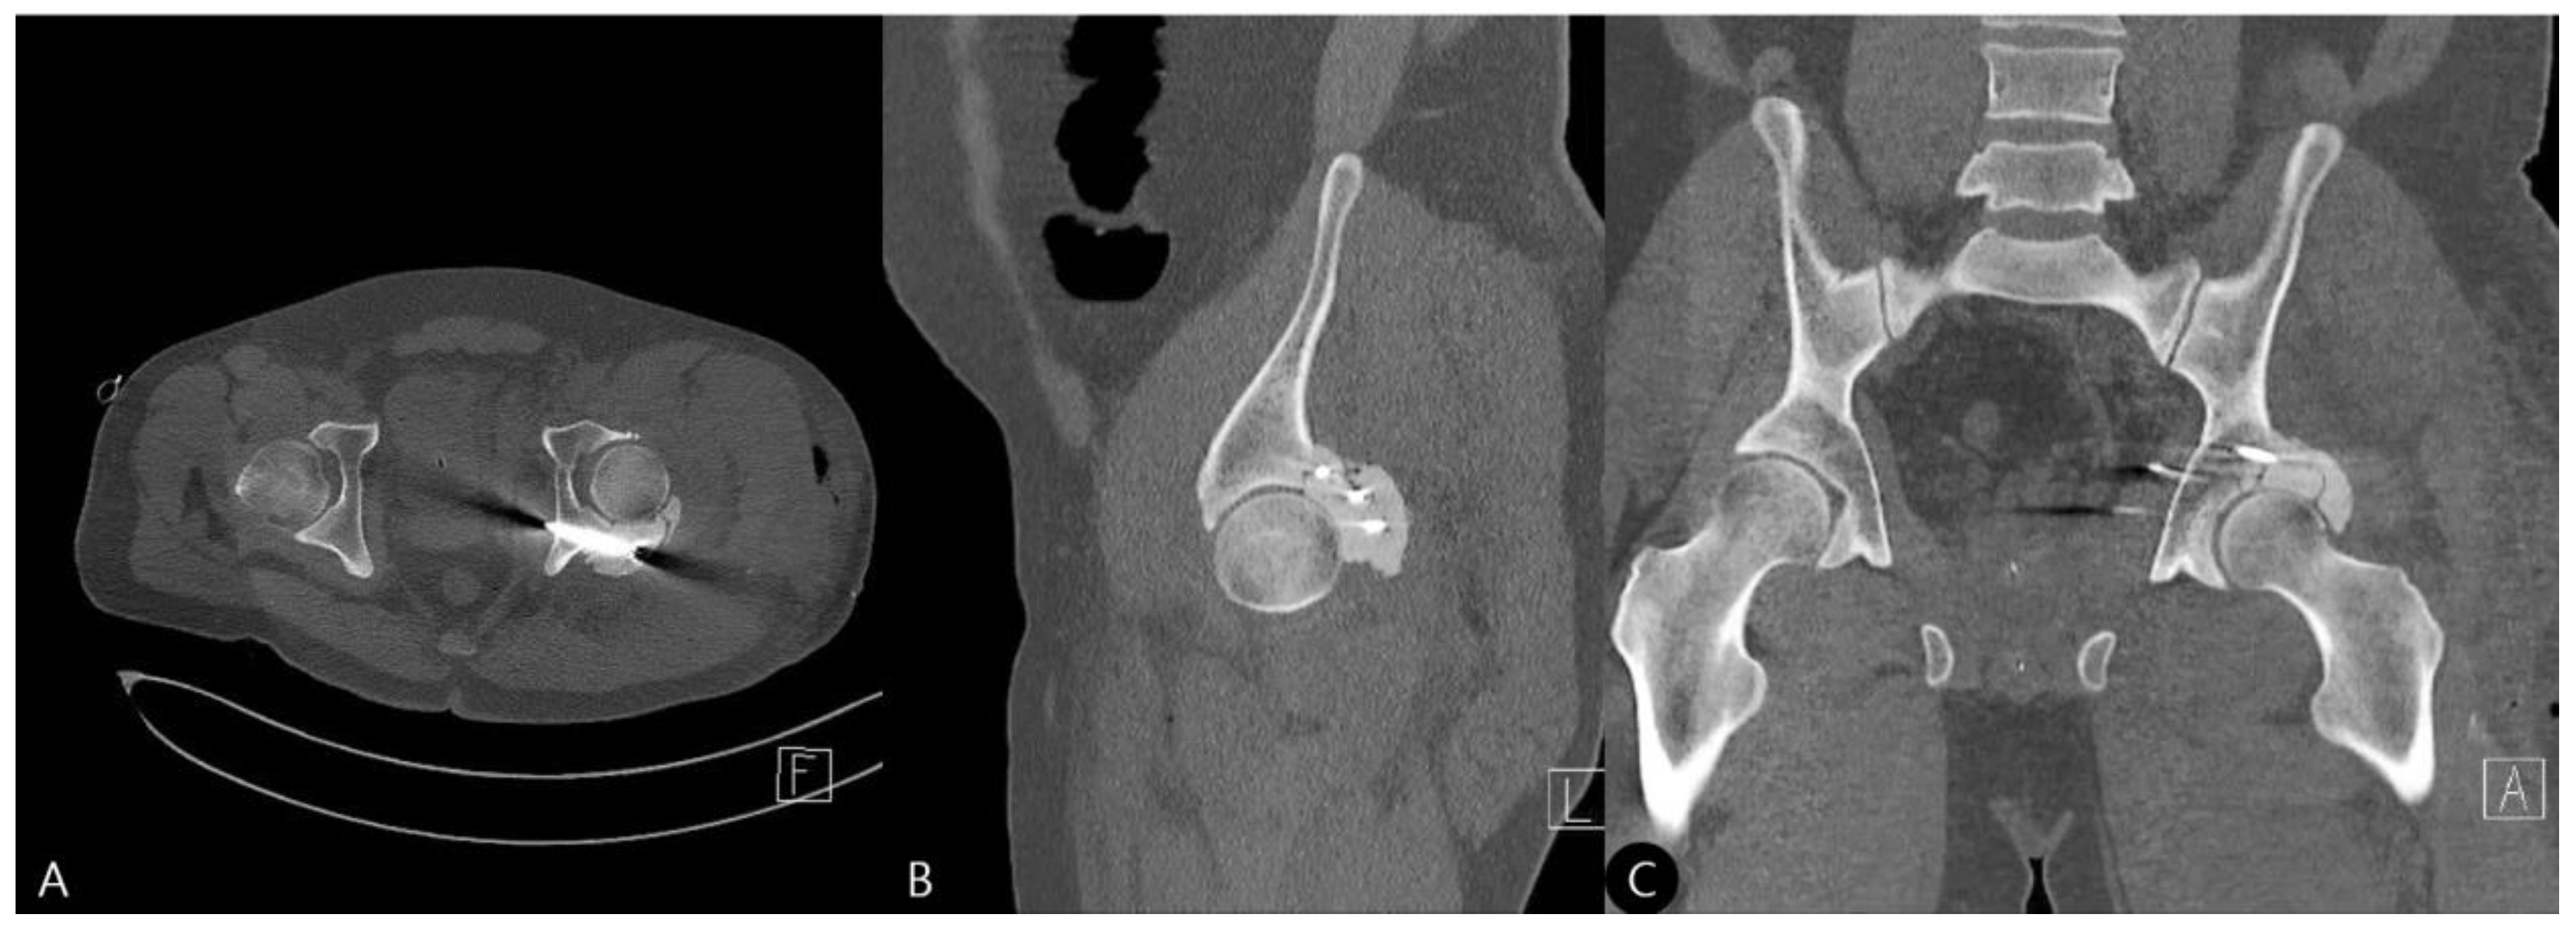

- 15 Months: A CT scan showed a stable joint, concentric reduction, and no signs of screw loosening or osteolysis (Figure 8). The patient reported no functional limitations. The mHHS was 82/100.